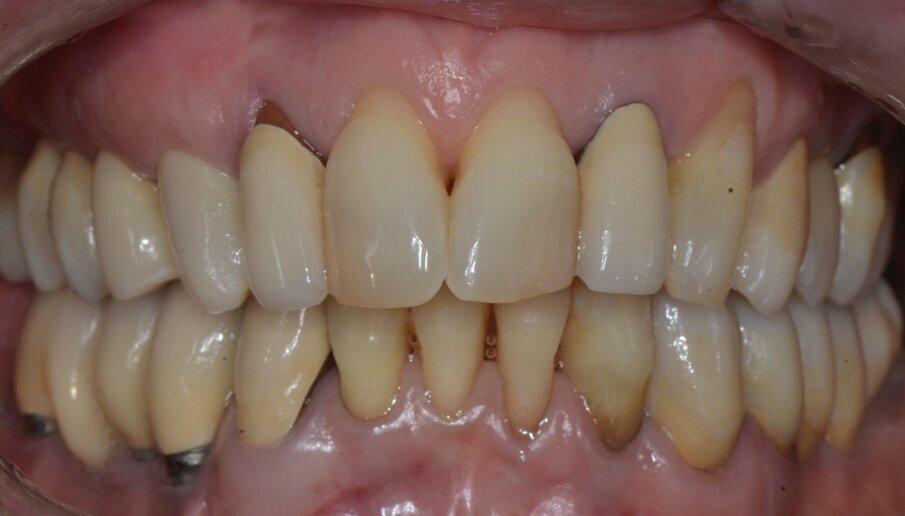

Riguardo al comparto intraorale, dalle radiografie diagnostiche e dall’esame parodontale e occlusale sono emersi aspetti che meritavano una correzione anche nei settori posteriori, ma la paziente ha deciso di effettuare inizialmente il trattamento dei soli gruppi frontali superiore e inferiore demandando a un momento successivo le problematiche dei quadranti posteriori (Figg. 2-6). Nel gruppo frontale superiore si possono notare recessioni gengivali sugli incisivi centrali, che sono anche molto ruotati, e sul canino di sinistra; corone in metallo-ceramica sugli incisivi laterali con esposizione del bordino metallico e una corona in ceramica metal-free sul canino di destra. Inoltre è molto evidente lo squilibrio delle parabole gengivali tra i due canini, per cui per ristabilire un’estetica ottimale sarà necessario anche interessare i tessuti molli eseguendo una chirurgia resettiva sul canino di destra e, al contrario, un lembo a posizionamento coronale sul canino di sinistra (Fig. 7).